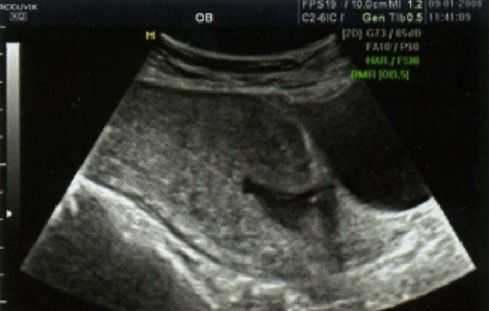

Рисунок 1 | Состоятельный рубец на матке

Рисунок 2 | Частично несостоятельный рубец. Определяются истончение миометрия и соединительнотканные включения в области рубца

Рисунок 3 | Несостоятельный рубец. Выявляется «ниша» в области рубца, миометрий не определяется

В течение беременности для оценки состояния рубца матки наиболее часто применяется ультразвуковое исследование, в ходе которого определяется эхоструктура и толщина рубца на всем протяжении, наличие кровотока в нем. К ультразвуковым маркерам несостоятельности рубца относят визуализацию дефекта миометрия в проекции рубца в виде «ниш» со стороны полости матки и обнаружение признаков некроза миометрия. Отсутствие кровотока в рубце служит неблагоприятным признаком в пользу несостоятельности рубца или его неполной состоятельности. По данным различных авторов, толщина рубца, при которой его можно назвать состоятельным, колеблется от 2 до 4-5 мм (при доношенном сроке), при этом учитывается равномерность его толщины на всем протяжении — то есть тонкий, но имеющий одинаковую на всем протяжении толщину рубец считается более надежным.